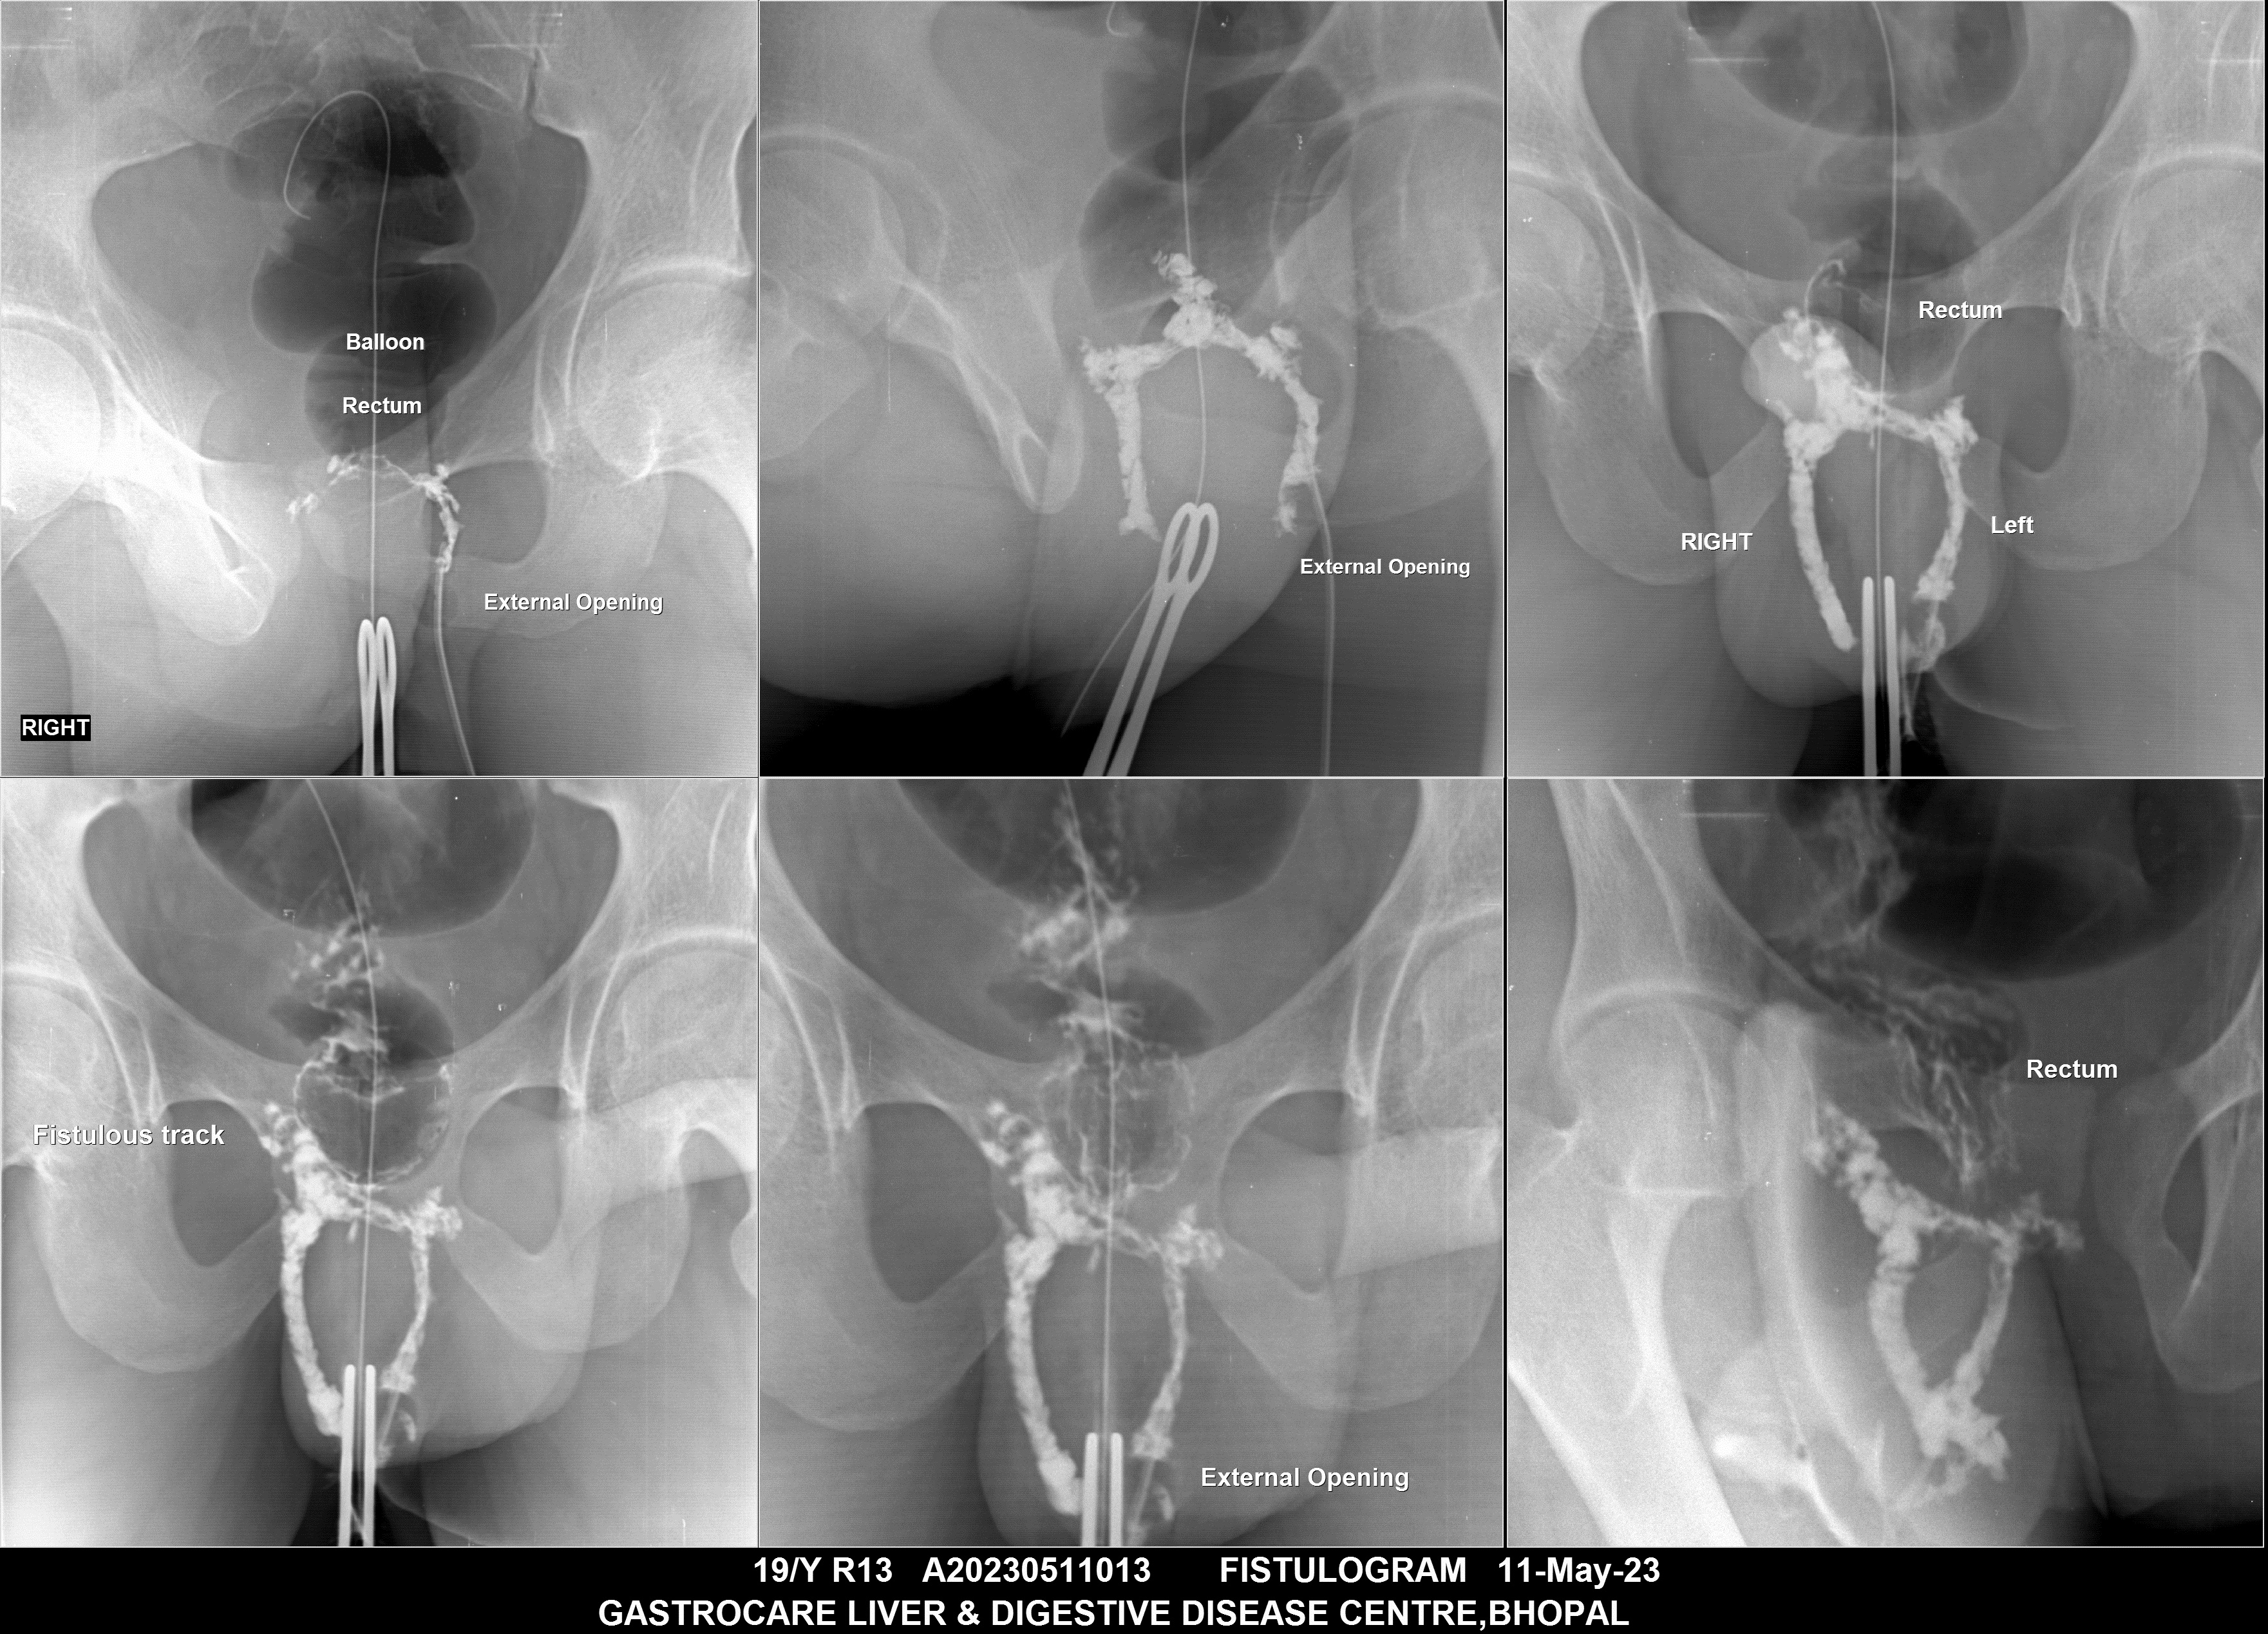

Section: FISTULOGRAM Total: 8 images

BaM Enteroclysis Loopogram BaE Fistulogram Urethrogram HSG